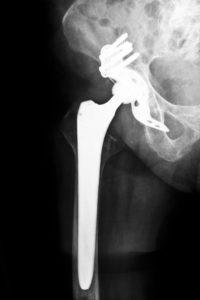

The DePuy ASR XL Acetabular System first became available in the United States in 2005. These metal-on-metal hips were marketed as being more durable than ceramic or plastic models. The FDA has received approximately 400 complaints from patients who received ASR hip replacements since 2008, and nearly 12% of patients needed revision surgery. DePuy issued a recall of the Depuy ASR XI in August 2010, which included 93,000 implants worldwide, after data concluded that the five year failure rate of this product is 1 out of 8 patients.

- Device failure from loosening – a result from bone loss

- Dislocation – two parts of the implant move against one another and become misaligned

- Fracture – bone around the implant breaking

- Loosening in the hip joint – implant fails to stay attached to the bone in the correct position